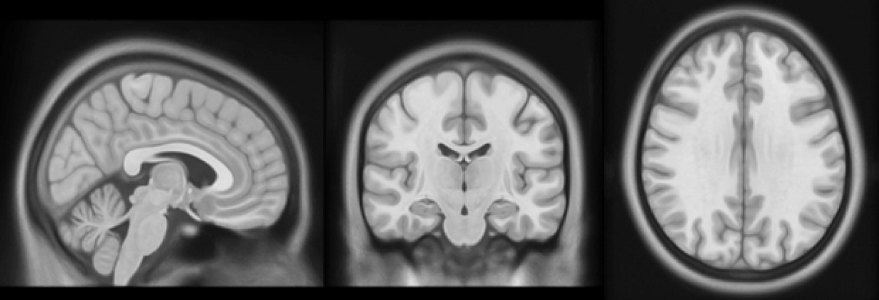

– Nowością jest fakt, że badania były prowadzone w sposób podłużny, czyli każdy uczestnik badania był skanowany trzykrotnie – wyspany, po zarwanej nocy i po pięciu dniach niewystarczająco długiego snu, około pięciu godzin na dobę. Korzystaliśmy z rezonansu magnetycznego – przy jego użyciu skanowaliśmy mózg. Mogliśmy dzięki temu spojrzeć zarówno na jego anatomię, jak i funkcjonowanie. Do analizy tych danych wykorzystaliśmy teorię grafów, dzięki czemu udało nam się szczegółowo zmapować sieć połączeń funkcjonalnych w mózgu  – tłumaczy Patrycja Ściślewska.

– Sprawdzaliśmy, po pierwsze, czy deprywacja snu będzie miała wpływ na aktywność mózgu, a po drugie – czy te dwa typy deprywacji różnią się od siebie – mówi Patrycja Ściślewska i dodaje: – Okazało się, że brak snu powoduje zmiany, ale w zależności od typu ulegają im inne obszary mózgu. Dla tego narządu to są dwa różne scenariusze. Jest to przełomowy wniosek płynący z naszych badań.

Wskutek niedoboru snu upośledzeniu ulegają funkcjonalne połączenia między obszarami mózgu. W szczególności wrażliwe są tzw. „huby” – obszary mózgu, które charakteryzują się największą liczbą połączeń. Mózg kompensuje sobie utratę połączeń, tworząc nowe drogi przepływu informacji. Wykorzystując uczenie maszynowe, naukowcy potrafią rozpoznać, czy dany obraz połączeń w mózgu należy do osoby chronicznie niewyspanej, czy do osoby, która zarwała noc.